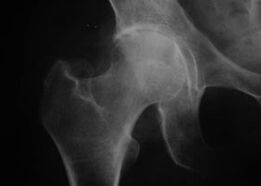

Coxatrosis, artrosis de la articulación de la cadera.

Radiografía de la articulación de la cadera con artrosis.

Con esta enfermedad se observa un cuadro clínico clásico de artrosis.

El primer síntoma de la coxartrosis es el malestar en la articulación de la cadera después de la actividad física.

Con la coxartrosis progresiva, aparecen aumento del dolor, rigidez y movilidad limitada.

Los pacientes que padecen una forma grave de coxartrosis respetan la extremidad afectada, evitan pisarla y, cuando están parados, eligen posiciones en las que el dolor sea mínimo.